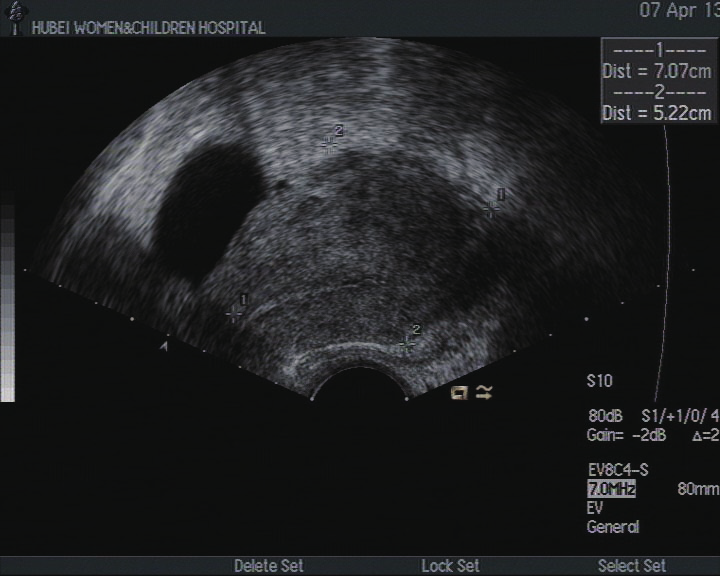

超声检查  2013 年 4 月 2 日,子宫切面形态失常,大小 7.1cm ×4.9cm ×5.2cm ,边界清,肌层光点分布不均匀。子宫左后壁可见 3.7cm ×4.2cm ×3.6cm 的低回声,边界清,向外突,周边可见血流信号,测得 RI:0.23。右侧角部可见 7.1cm ×9.0cm ×8.0cm 的低回声,其内回声不均并可见多个不规则的无回声,其中一个大小为 4.0cm ×2.3cm ;其中低回声内可见丰富的血流信号,测得 RI:0.32。内膜可显示,厚度 0.32cm ,内未见明显异常血流信号。彩色多普勒:肌层血流可显示。右侧卵巢因肠干扰显示不清。左侧卵巢内可见多个无回声,其中最大一个为 3.1cm ×2.5cm 。宫颈前后径 2.9cm 。陶氏腔内见 1.1cm ×2.3cm ×1.0cm 的液性暗区。提示:子宫声像图改变(子宫肌层侵蚀性病灶可能);左侧卵巢囊肿;陶氏腔少量积液。

图A 超声图像(2013 年 04 月 02 日,化疗前)